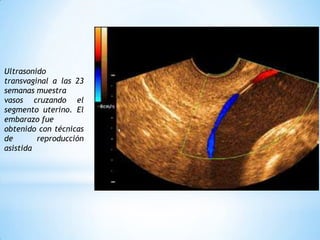

Vasa previa se refiere a cuando los vasos sanguíneos pasan a través del cuello uterino, lo que puede causar hemorragia fetal severa durante el parto. Puede ocurrir en 1.5-4 de cada 10,000 embarazos y es más común en embarazos múltiples o concebidos con fertilización in vitro. Se diagnostica mediante ultrasonido transvaginal a las 23 semanas para identificar vasos que crucen el segmento uterino. El manejo incluye parto por cesárea programada antes de las 37 semanas para